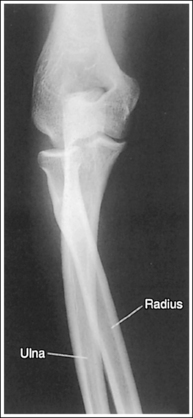

The distal and proximal forearm is positioned in an AP projection. The radial styloid is demonstrated in profile laterally, and superimposition of the metacarpal bases and of the radius and ulna is minimal.

• To obtain an AP projection of the distal forearm, supinate the hand and place the second through fifth metacarpal heads against the IR (Figure 4-59).

• Detecting distal forearm rotation. Rotation of the distal forearm results from inaccurate positioning of the hand and wrist. If the wrist and hand are not positioned in an AP projection but are rotated, the radial styloid is no longer in profile and the distal radius and ulna and metacarpal bases are superimposed. To identify which way the wrist is rotated, evaluate the metacarpal and carpal bones. When the wrist and hand are internally rotated, the laterally located first and second metacarpal bases and carpal bones are superimposed, and the medially located metacarpals, pisiform, and hamate hook are better demonstrated (see Images 65 and 67). If the wrist and hand are externally rotated, the medially located fourth and fifth metacarpal bases and carpal bones will be superimposed, whereas the laterally located metacarpals and carpal bones will demonstrate less superimposition.

The ulnar styloid is projected distally to the midline of the ulnar head.

• The position of the ulnar styloid is determined by the position of the humerus and elbow. When the humerus and elbow positions are adjusted but the wrist position is maintained, it is the ulna that rotates and changes position. Positioning the humeral epicondyles parallel with the IR for the AP projection of the forearm places the ulnar styloid posterior to the head of the ulna. If the elbow is rotated internally and the wrist remains in an AP projection, the ulnar styloid is demonstrated laterally, next to the radius. If the elbow is rotated externally and the wrist remains in an AP projection, the ulnar styloid is demonstrated in profile medially.

The anterior and posterior carpal articulating surfaces of the distal radius are superimposed, and the radioscaphoid and radiolunate joint spaces are open.

• The distal radial carpal articular surface is concave and slants at approximately 11 degrees from posterior to anterior. When the forearm is placed parallel with the IR in an AP projection and the central ray is centered to the midforearm, diverged x-rays record the image much as if the central ray were angled toward the wrist joint. If this angle of divergence is parallel with the AP slant of the distal radius, the resulting image shows superimposed distal radial margins and open radioscaphoid and radiolunate joint spaces.

The proximal forearm is positioned in an AP projection. The radial head is superimposed over the lateral aspect of the proximal ulna by approximately 0.25 inch (0.6 cm). If included on the IR, the medial and lateral humeral epicondyles are demonstrated in profile at the extreme medial and lateral edges of the distal humerus.

• An AP proximal forearm projection is obtained by palpating the humeral epicondyles and aligning them parallel with the IR, placing the proximal radius anterior to the ulna (see Figure 4-59).

• Detecting proximal forearm rotation: Proximal forearm rotation results when the humeral epicondyles are poorly positioned. Rotation can be identified on the image when the radial head demonstrates more or less than 0.25 inch (0.6 cm) superimposition on the ulna and when the humeral epicondyles are not visualized in profile. When more than 0.25 inch (0.6 cm) of the radial head is superimposed over the ulna, the elbow has been internally rotated (see Image 74). When less than 0.25 inch (0.6 cm) of radial head is superimposed over the ulna, the elbow has been externally rotated (see Image 67).

The radial tuberosity is demonstrated in profile medially, and the radius and ulna appear parallel.

• When the distal humerus is positioned with the epicondyles parallel with the IR, the relationship of the radius and ulna is controlled by wrist positioning. To place the radius and ulna parallel and the radial tuberosity in profile medially, position the wrist and hand in an AP projection. When the hand and wrist are pronated, the radius crosses over the ulna, and the radial tuberosity is rotated posteriorly, out of profile (see Image 68).